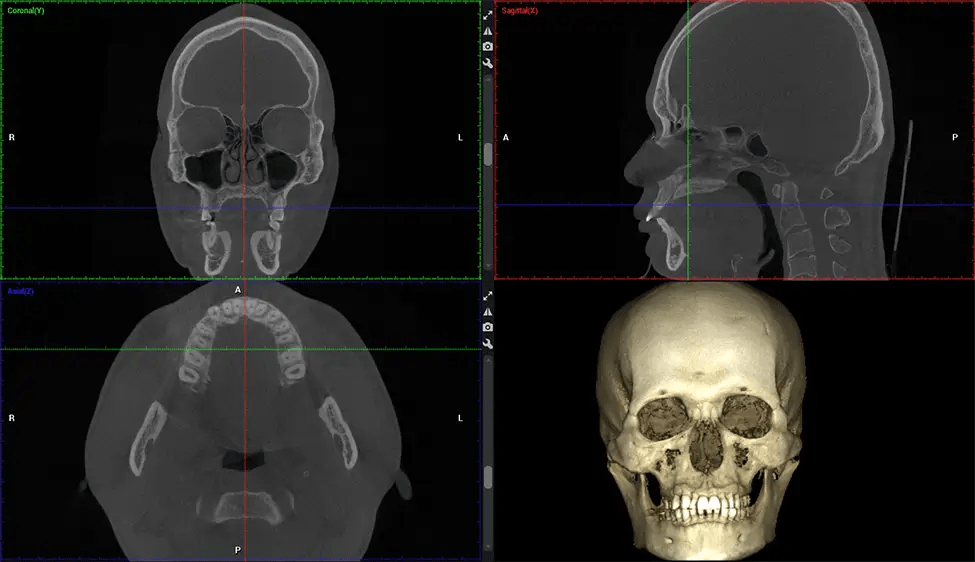

Cone Beam Computed Tomography (CBCT) is an advanced imaging technique used in dentistry and maxillofacial surgery to obtain detailed 3D images of the oral and maxillofacial structures. At Dr G Dental Studio, our CBCT scanners utilize a cone-shaped X-ray beam and a specialized detector to capture images from different angles. A computer then combines these images to create a 3D representation of the patient’s oral anatomy.

The patient is first positioned in the CBCT scanner, which typically consists of a rotating arm that houses the X-ray source and a detector. The patient’s head is immobilized to ensure accurate image capture. The X-ray source and detector rotate around the patient’s head, capturing various X-ray images from multiple angles. As the X-ray source rotates, it emits the cone-shaped X-ray beam towards the detector. The detector captures the X-ray images, which are then processed by the CBCT software.

After the scanning process, the captured X-ray images are processed by the CBCT software, which applies algorithms to reconstruct a detailed 3D image of the scanned area. The software compiles these individual X-ray images and creates a digital 3D representation of the patient’s anatomy. The reconstructed 3D CBCT image can be viewed and analyzed by the dentist or radiologist. This image can be manipulated, rotated, and zoomed in or out to examine specific structures and evaluate the patient’s condition.

Planmeca Viso G7 CBCT ( Cone Beam CT Scan ) is designed to surpass the demands of industry leaders, specialists, and large institutions. It’s has a large ø25×30 cm sensor with four built-in cameras. It can capture unlimited volume sizes from a ø3×3 cm to a ø30x30cm volume capturing the skullcap through C7 on the cervical spine. The Planmeca Viso G7 offers the industry’s largest single volume scan of ø30×19 cm. It’s poised to handle advanced imaging modalities such as Planmeca ProFace® and Planmeca 4D™ Jaw Motion technology. The occipital head support allows an unimpeded view of facial tissue.